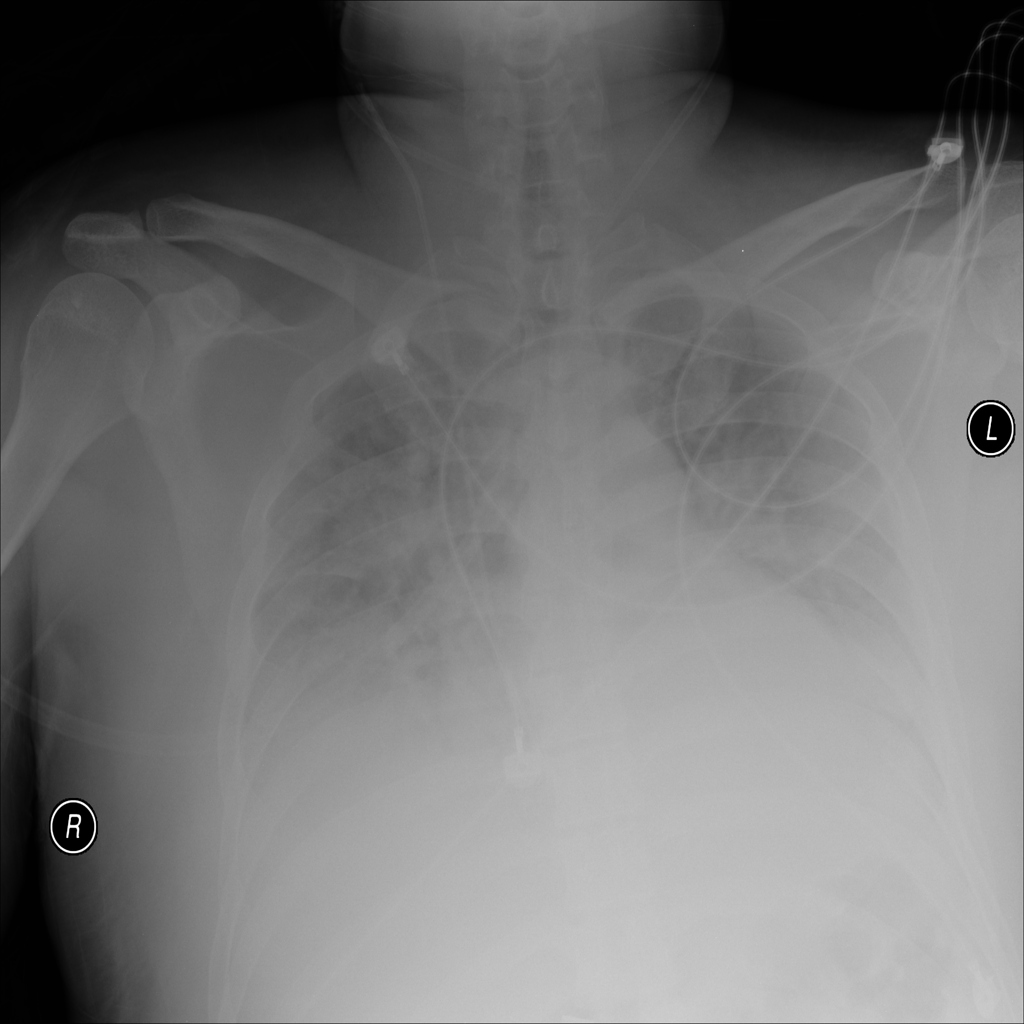

PAT-E828 · IMG-005Edema

PAT-E828 · IMG-005

AP